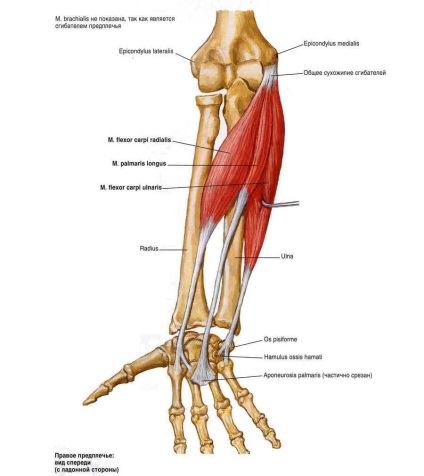

Az izomszövet, amelyek körül a könyök, kezdve a váll vagy alkar. Úgy elején vagy végén kívül a könyökét. De vannak bizonyos izomcsoportokat, amelyek közvetlen hatással vannak a munka a könyök, és közel van hozzá. Váll izmait, amelyek befolyásolják a működését a könyök készülék, 2 csoportra osztjuk. Az 1 tartalmazza flexor:

alkar hajlító

Az emberi anatómia jelzi, hogy minden, az alkar hajlító osztva 2 csoportban. Ez a berendezés felületes és mély rétegeket. A felületi réteg közé tartoznak:

- Hengeres borintóizom.

- Radial flexor.

- Ulnaris flexor.

- Felületes flexor digitorum.

Hengeres borintóizom karját a könyök fontos feladat. Serkenti az alkar pronatiós és a mozgás a készülék. Ha meghibásodás pronator mobilitás mechanizmus részben kitört. Pronator zajlik a condylusa humerus csont és a csont. Ha a munka gép elromlott, akkor kiegyenesedik vagy meghajlítani alkar egyszerűen lehetetlen. Ez fájdalmat okoz a betegnek, és előírja, azonnali látogatást az orvos.

Orsócsonti csuklóhajlító izom olyan elem, amely hasonlít egy orsóval. Ez csatlakozik a szomszédos csontra. Az alján kíséri ín. Radial flexor összeköti a könyök és a csukló. Anatómiája a könyök eszköz nem lehetséges anélkül, hogy a radiális flexor. Ellátja nagyon fontos funkciót. Rajta múlik a mobilitás a kéz, alkar hajlítása. Beam hajlító - többcsukiós izomszövet. Egy ember az is fontos, mert ez része a kéz és az alkar pronator. Ha a flexor csukló sérült, akkor az a személy nem tudja mozgatni a kefét, és a fájdalom is megnyilvánul az egész kezét.

Az anatómiai szerkezete a könyök flexor carpi 2 részből áll. A felkar feje van rögzítve a humerus és a singcsont - az alkar fascia. Distalis nyúlványt szövetet csatlakozik a borsócsont. Minden más szövetek, amelyek kapcsolódnak a borsócsont folytatta cselekedetért könyök flexor. Tevékenységek borsócsont szövetet azon a tényen alapul, hogy ez befolyásolja a növekedést az erők a könyök flexor. Ha a kár ezen elemének jelentős változások a működését a kéz nem fog megtörténni, de a beteg fájdalmat lehet érezni az egész kezét.

Felületes hajlító az ujjak között van rögzítve az ulnaris és radiális flexorok. Anatómiai magában foglalja a szétválás a flexor 4 részre. Ezek az izomszövet növekedését együtt, egy helyen, de eltérő rögzítési pontok később. Ez sokízületi egység és a felelős feszítve a metacarpophalangealis izomszövet.